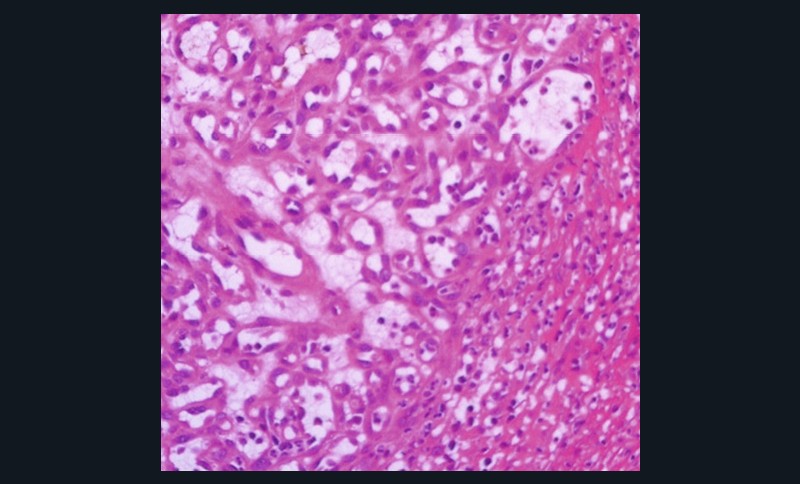

- Histologie : tissu conjonctif richement vascularisé + infiltrat massif de plasmocytes (fig. 1c).